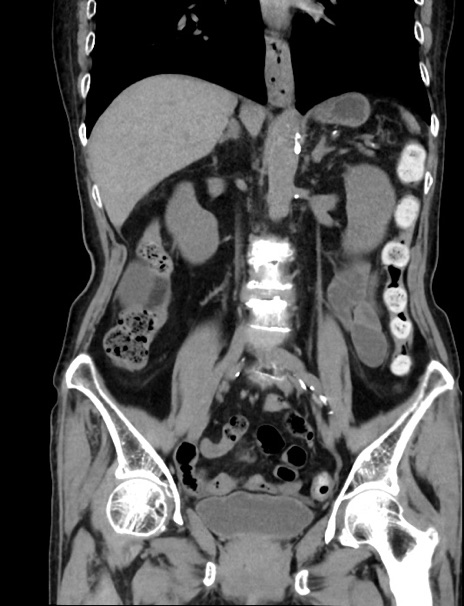

症例33(冠状断像)

【症例】70歳代 女性

【主訴】心窩部痛

【現病歴】延髄病変の精査・加療にて神経内科入院中。本日より心窩部痛あり。

【既往歴】虫垂炎

【身体所見】右下腹部を中心に圧痛と反跳痛あり。

【データ】WBC 10900、CRP 0.02